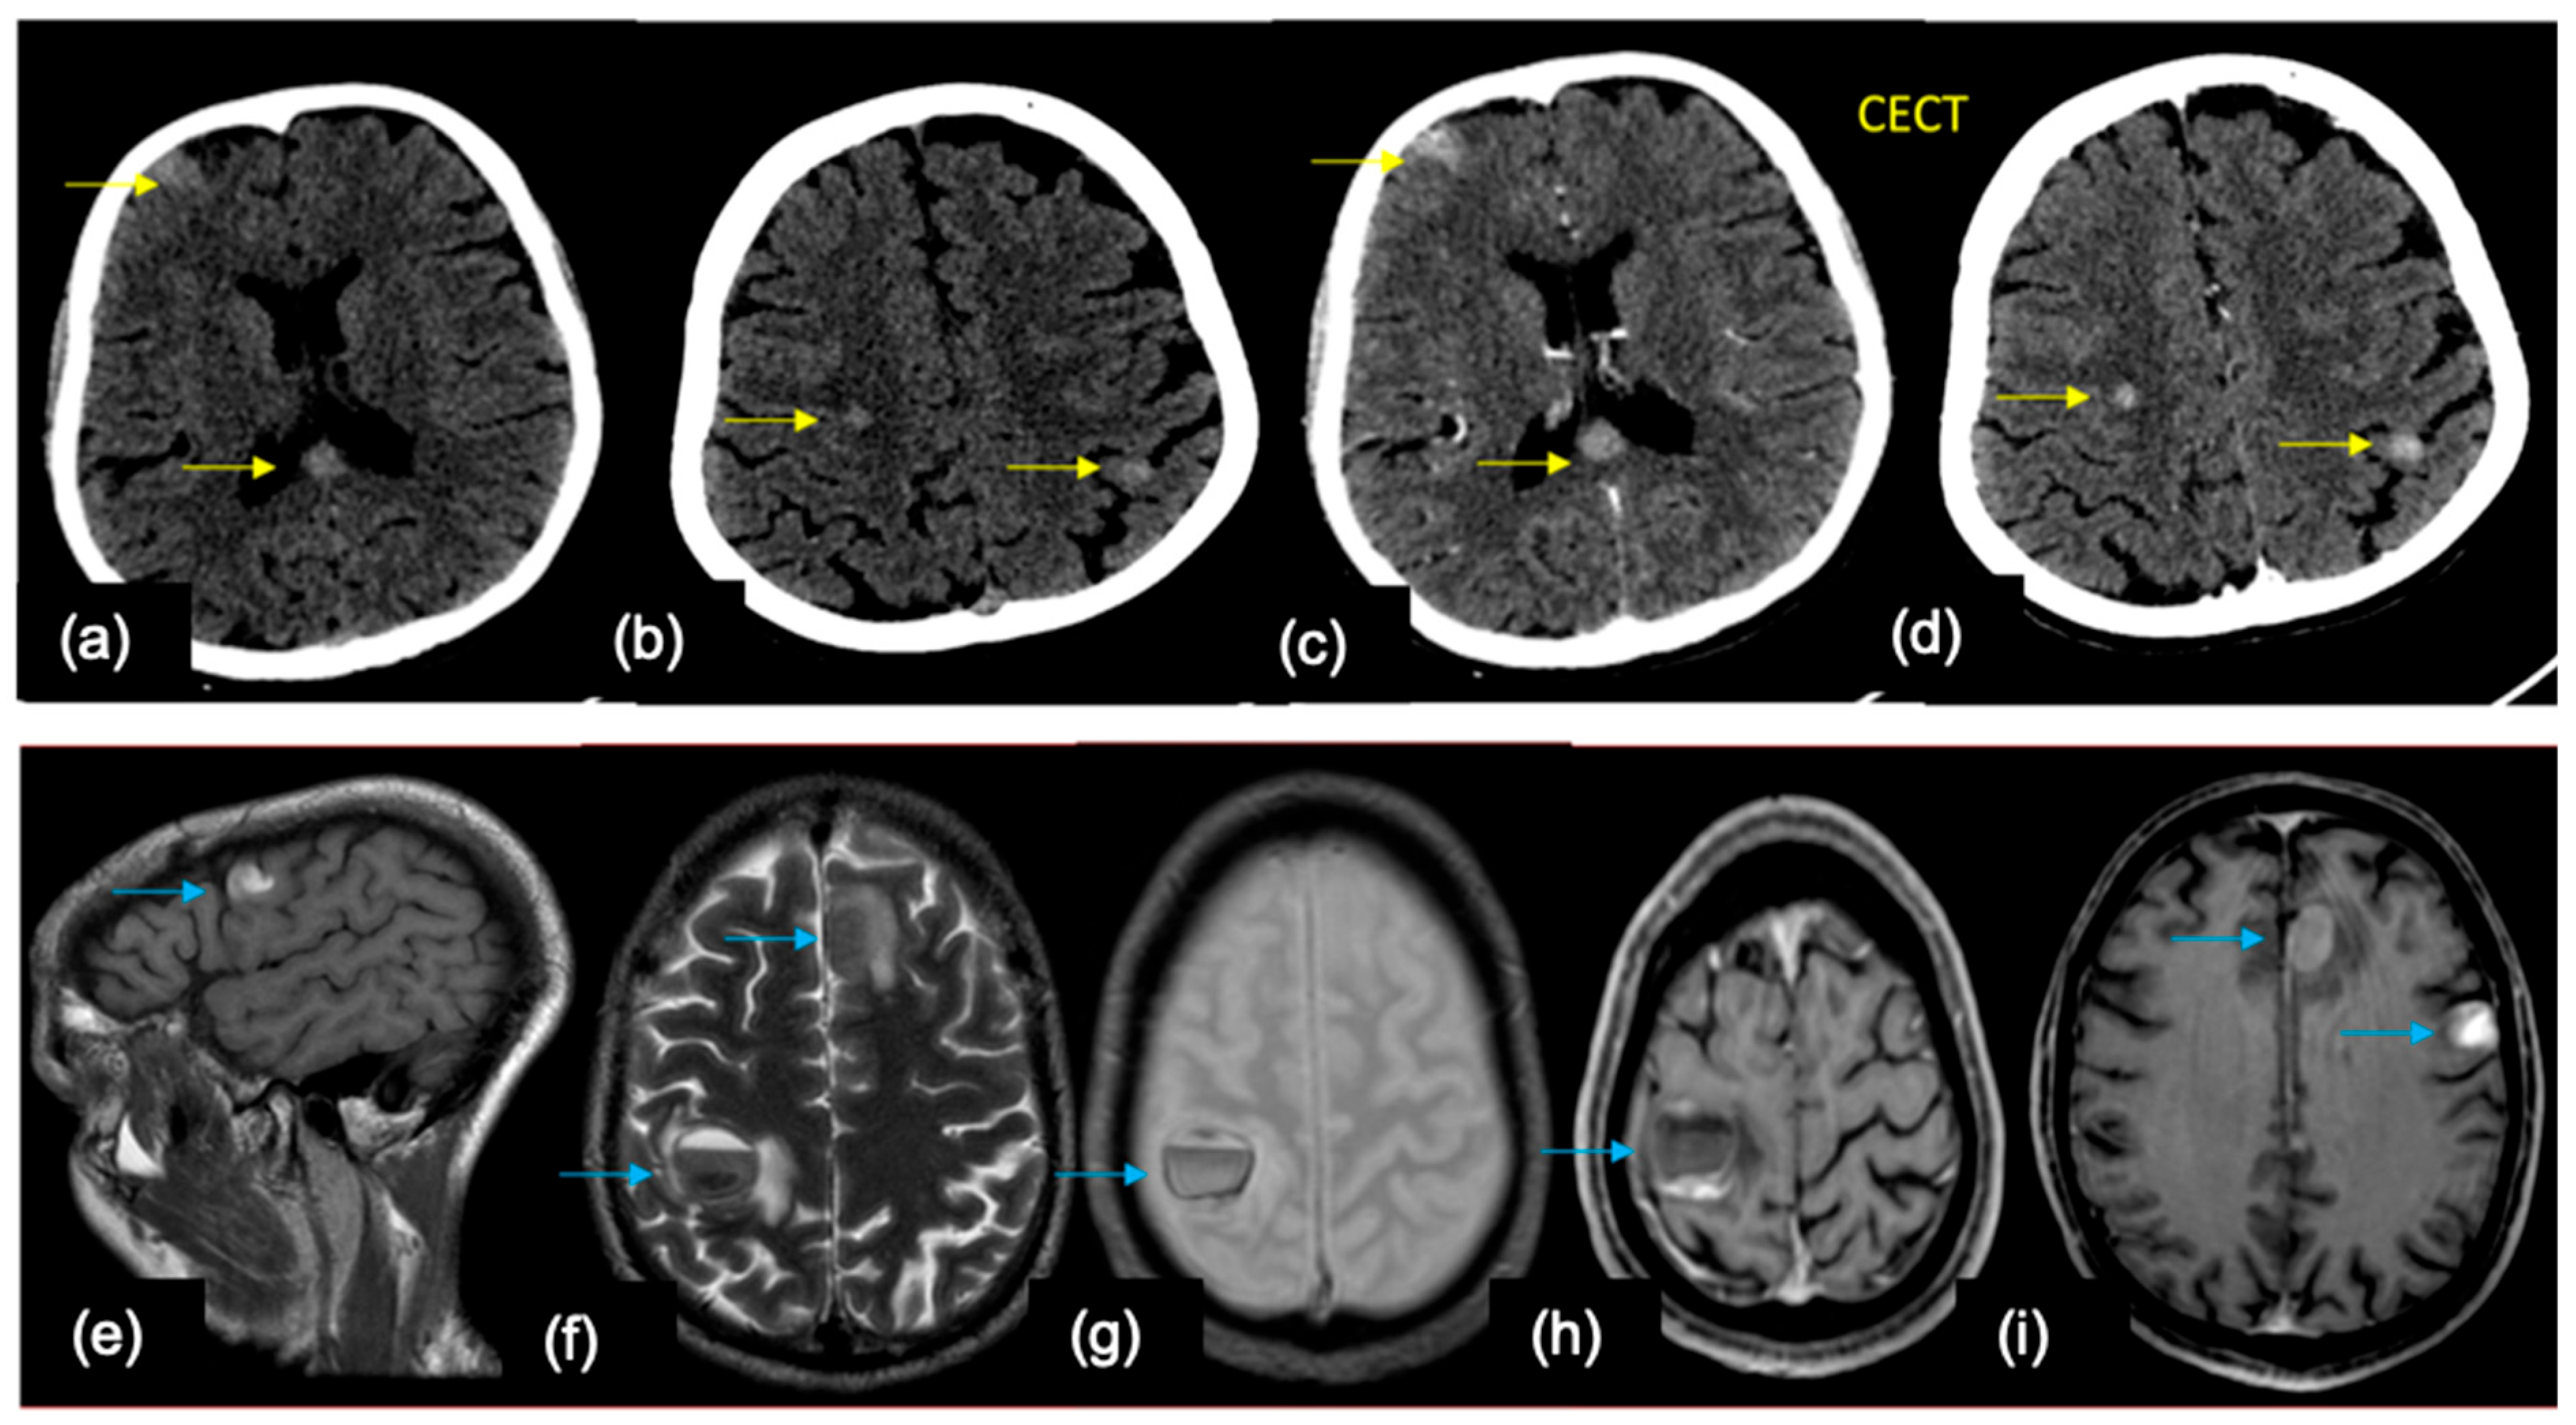

5.2. Role of Imaging in Diagnosis

7. Imaging Aspects of Specific Primary Tumor Biology

7.1. Lung

7.2. Breast

7.3. Others